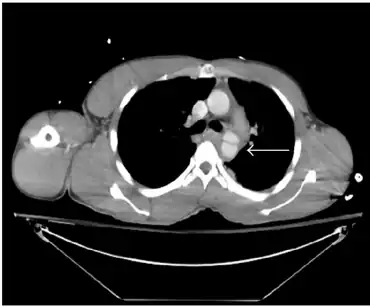

The gold standard for diagnosis of thoracic aortic injury is aortography. This method involves inserting a catheter into the aorta and directly injecting contrast material. The primary benefit of aortography is the ability to precisely determine the location of injury for surgical planning.[4] Another imaging modality is CT angiogram which has a sensitivity of 100%.[4] A CT angiogram relies on timing the CT scan after a bolus of IV contrast is administered from a peripheral IV site. Since a CT angiogram has a sensitivity of 100% and less invasive due to the peripheral placement of the IV line than aortagraphy it is the primary imaging choice.[4] This allows visualization of the aorta and provides precise locations of traumatic injury.[5] A CT angiogram does show both direct and indirect signs of aortic injury. The indirect sign that you can see is effacement of fat due to a hematoma.[2] This sign should clue in a radiologist that there is an underlying injury. Some direct signs from a CT include having an intimal flap, irregularity of the shape of the aorta, filling defects secondary to a thrombus, or out pouching of the aorta.[2]

However, non contrasted CT scans, chest X-rays, and transesophageal echos can also be used. Chest X-rays most sensitive finding is a widened mediastinum of greater than 8 cm.[4] An apical cap and displacement of the trachea to either side of the chest from midline can also be seen.[5] A normal chest X-ray, however, does not exclude a diagnosis of thoracic aortic injury.[4] A chest X-ray can also be useful to diagnose subsequent problems caused by aortic rupture such as pneumothorax or hemothorax.[5] Non contrasted CT scans might show an intimal flap, periaortic hematoma, luminal filling defect, aortic contour abnormality, pseudoaneurysm, contained rupture, vessel wall disruption, active extravasation of intravenous contrast from the aorta and is therefore useful to assess for minimal aortic injury.[5] Trans esophageal echos are useful in patients that are hemodynamically unstable, but the sensitivity and specificity of this study varies based on clinical user.[4] The trans esophageal echo relies on placement an ultrasound probe into the patient's esophagus in order to get an ultrasound of the heart. If esophageal injury is expected, the patient has a facial injury, or if the patient has difficulty maintaining their away then the trans esophageal echo is contraindicated.[9]